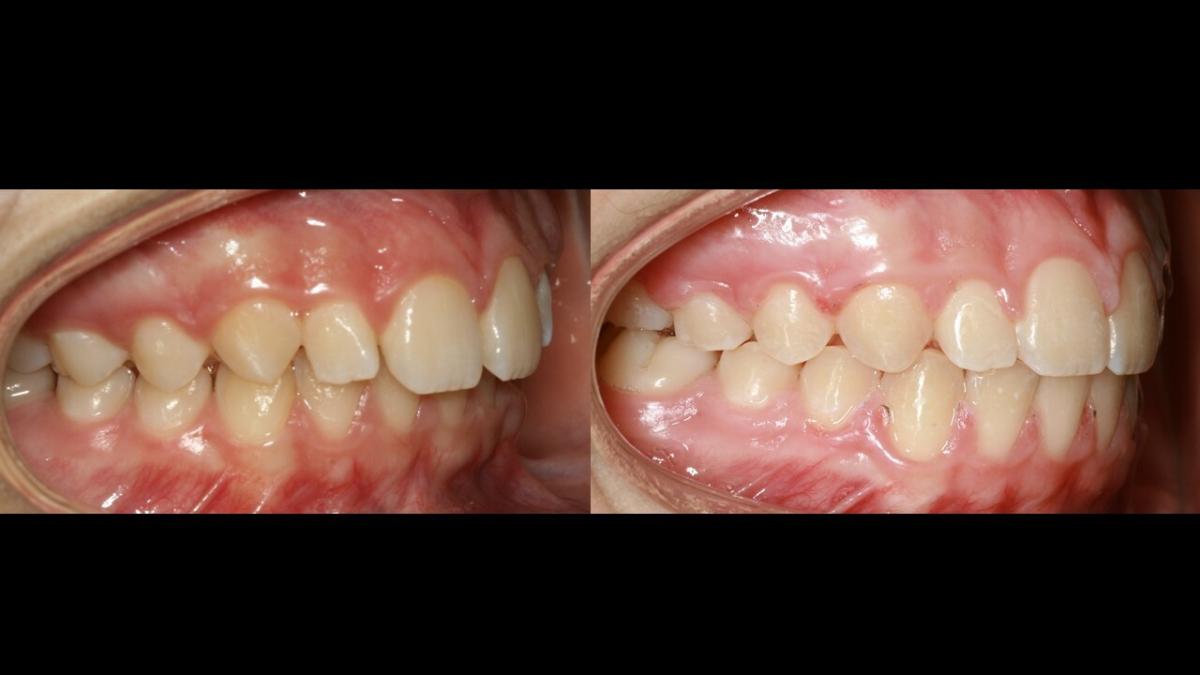

large-Avance de mordida